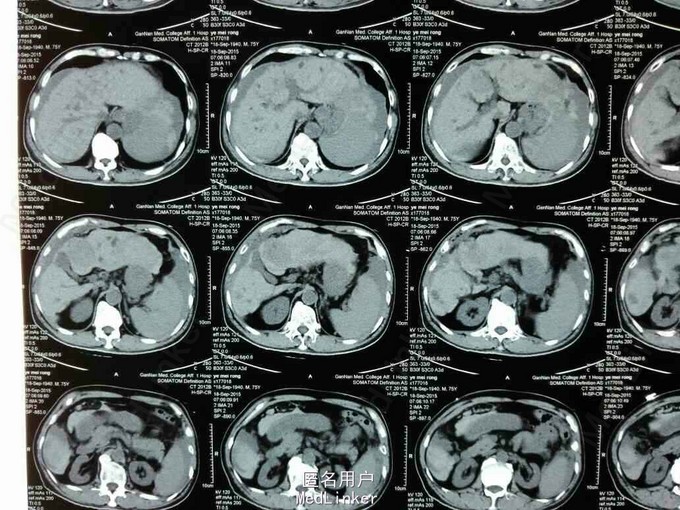

患者,男性,75岁,因“右上腹痛9小时”入院。既往有乙肝病毒肝炎病史,未予治疗。

查体:贫血貌,生命体征平稳,腹稍硬,可及压痛和反跳痛。辅查:肝脏弥漫性结节,考虑原发性肝癌,并破裂出血。AFP:1570ng/L。

诊断:原发性肝癌并破裂出血。治疗:给予补液,止血对症处理后,行TACE术。